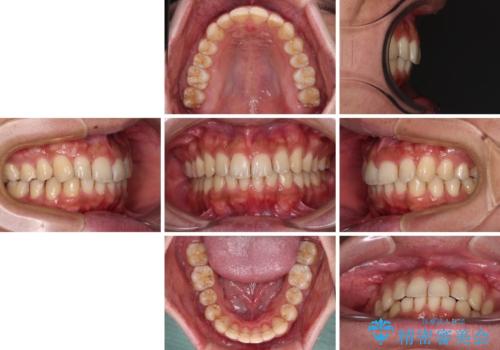

デコボコの改善はもちろん、下顎前歯が隠れてしまうディープバイトも一緒に改善することができ、奥歯への負担を軽減することができました。